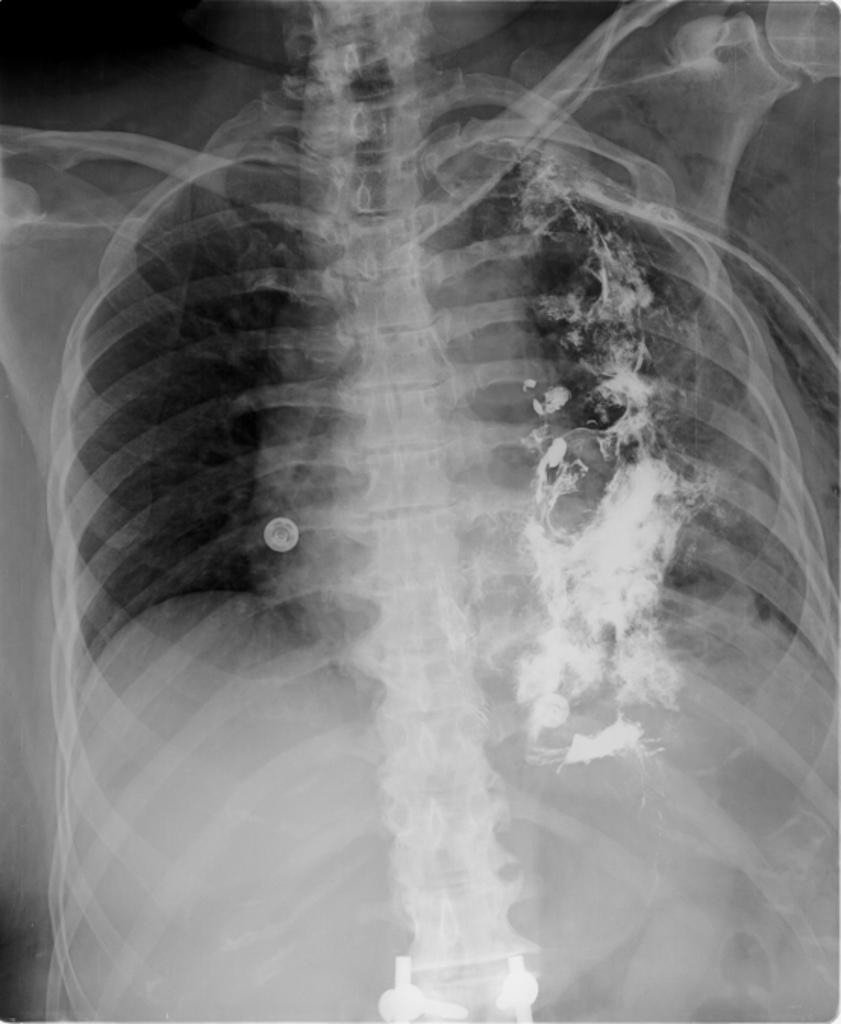

2823. Представленные на рентгенограмме данные наиболее характерны для